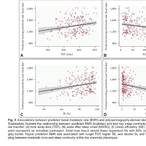

전립선암, 약물 치료 효과 예측 가능해진다... 맞춤 치료 기대감 쑥

- 2026-04-09 09:39

- 김용발 기자